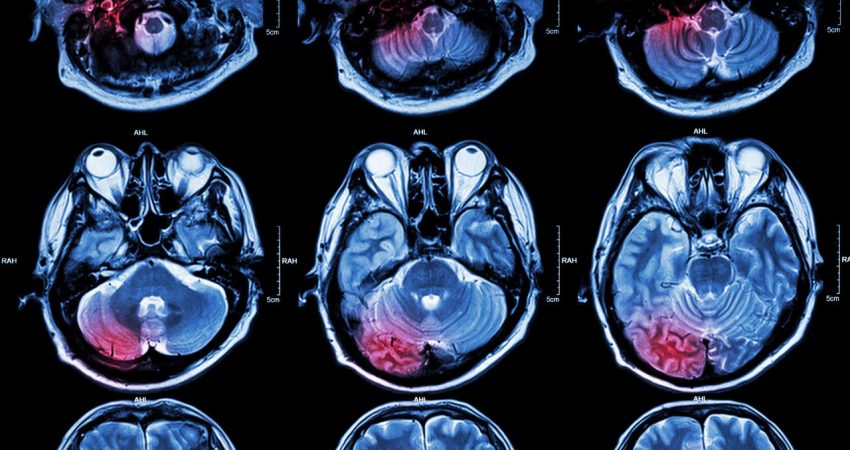

Për studimin e fundit, një ekip ekspertësh në Mbretërinë e Bashkuar dhe Kinë monitoruan aktivitetin e trurit në 34 vullnetarë duke përdorur skanerin e trurit.

Shikimi i imazheve lidhej me aktivitetin e reduktuar në zonën e trurit që kontrollon dhimbjen.

Studiuesit thanë se kjo tregon për një ‘lidhje funksionale’ midis ndikimeve nostalgjike dhe pjesës së trurit që përpunon dhimbjen.